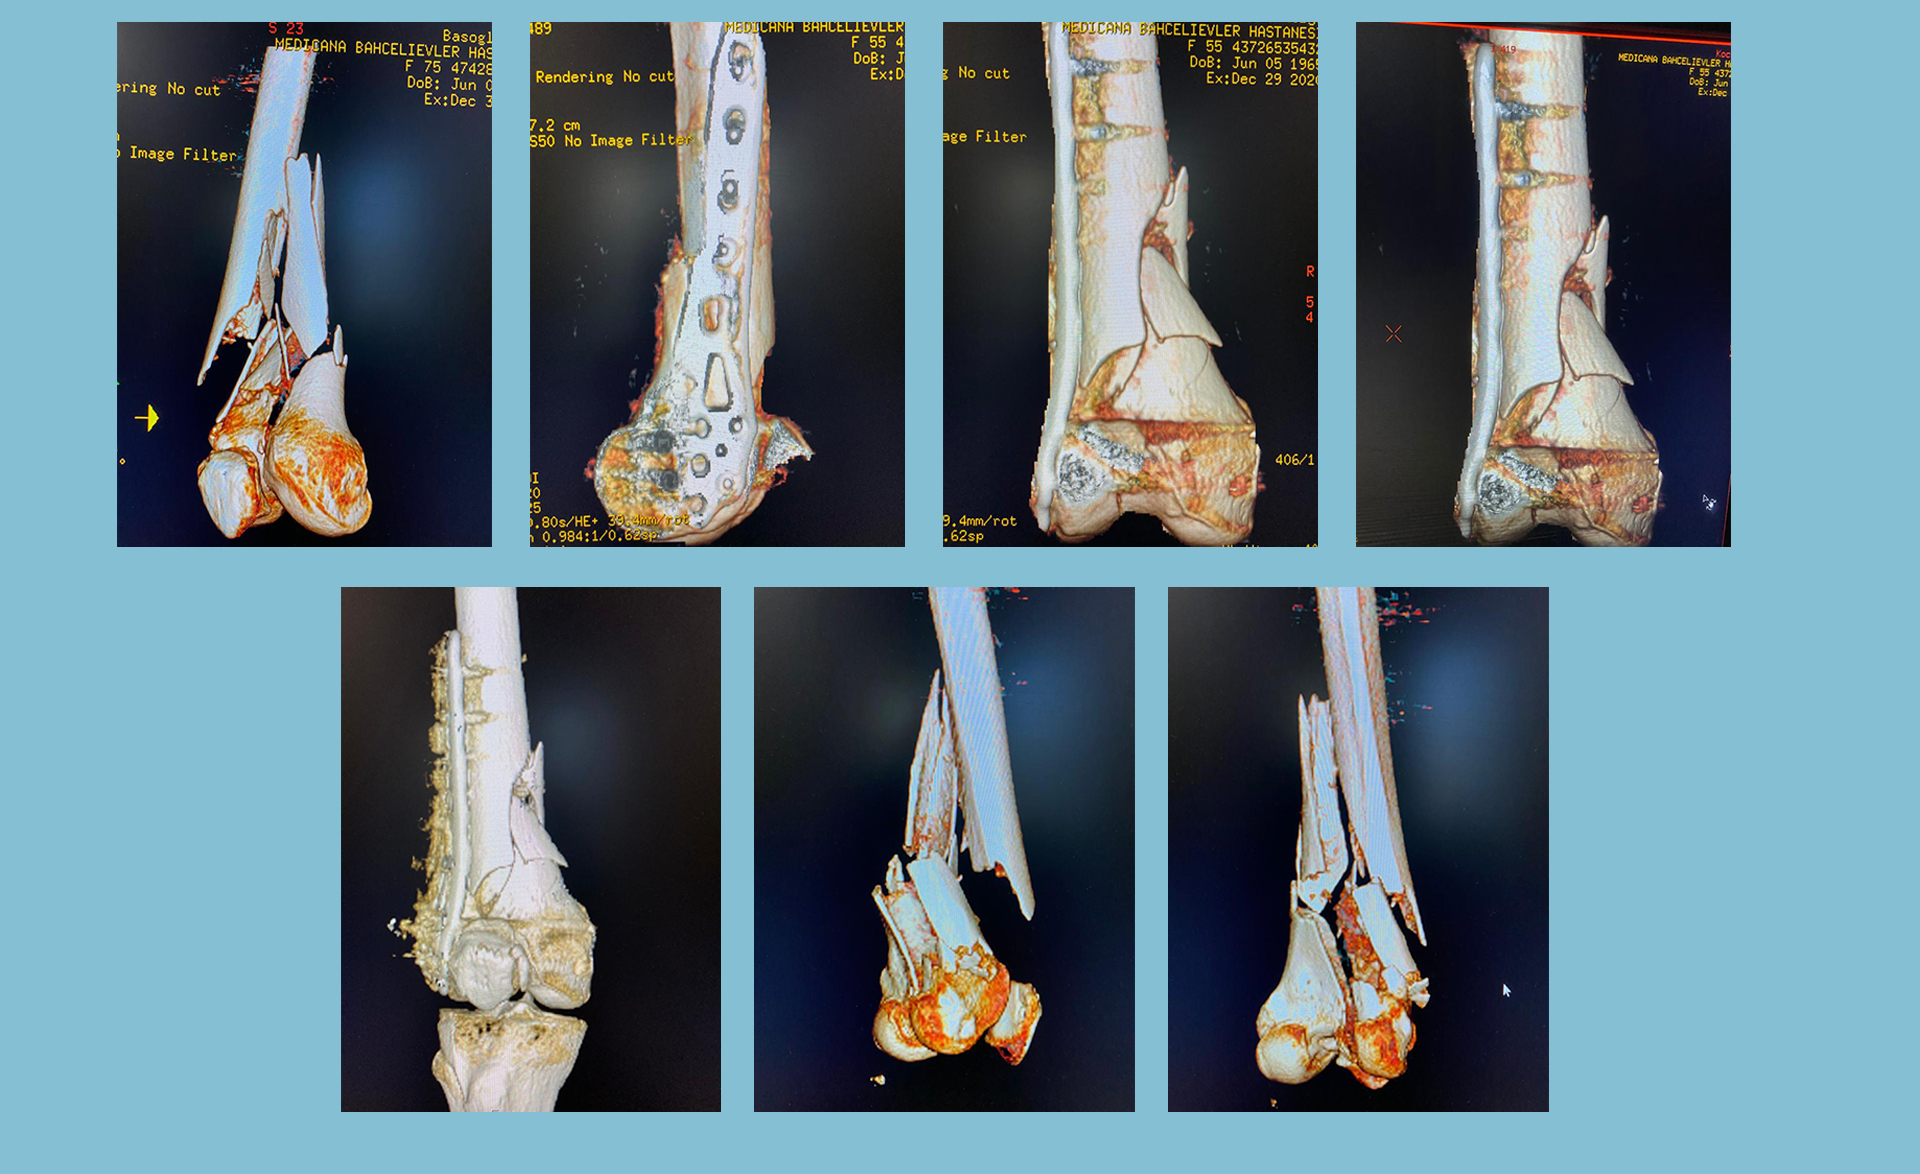

Ortopedik cerrahinin bir alt uzmanlığı olarak kabul edilir ve kırık kemiklerin tedavi edilmesine ve vücudun yaralı kısmının yaralanmadan önce sahip olduğu orijinal gücüne ve maksimum işlevine geri dönmesini sağlamaya odaklanır.